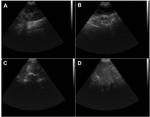

La figura 2 correspondiente a las imágenes del examen ecográfico abdominal que muestra al explorar la glándula mamaria lesiones compatibles con carcinoma sin evidencia de condición metastásica. Se reporta la presencia de masas heterogéneas de estructura irregular con áreas hipoecoicas e hiperecoicas con bordes mal definidos, vascularización aumentada, microcalcificaciones y áreas anecoicas dentro del tumor debido a degradación tisular. No se observa invasión local con extensión a tejidos adyacentes o alteración de los ganglios linfáticos regionales.

Figura 2. Imágenes de ecografía abdominal de un canino hembra Husky Siberiano de 10 años de edad. (A) Riñón izquierdo, (B) glándula mamaria, (C) glándula mamaria, (D) bazo.